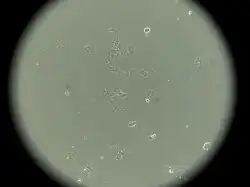

MCF-7 Cells

MCF-7 is a breast cancer cell line isolated in 1970 from a 69-year-old White woman.[1] MCF-7 is the acronym of Michigan Cancer Foundation-7, referring to the institute in Detroit where the cell line was established in 1973 by Herbert Soule and co-workers.[2] The Michigan Cancer Foundation is now known as the Barbara Ann Karmanos Cancer Institute.[3]

This cell line retained several characteristics of differentiated mammary epithelium, including the ability to process estradiol via cytoplasmic estrogen receptors and the capability of forming domes.